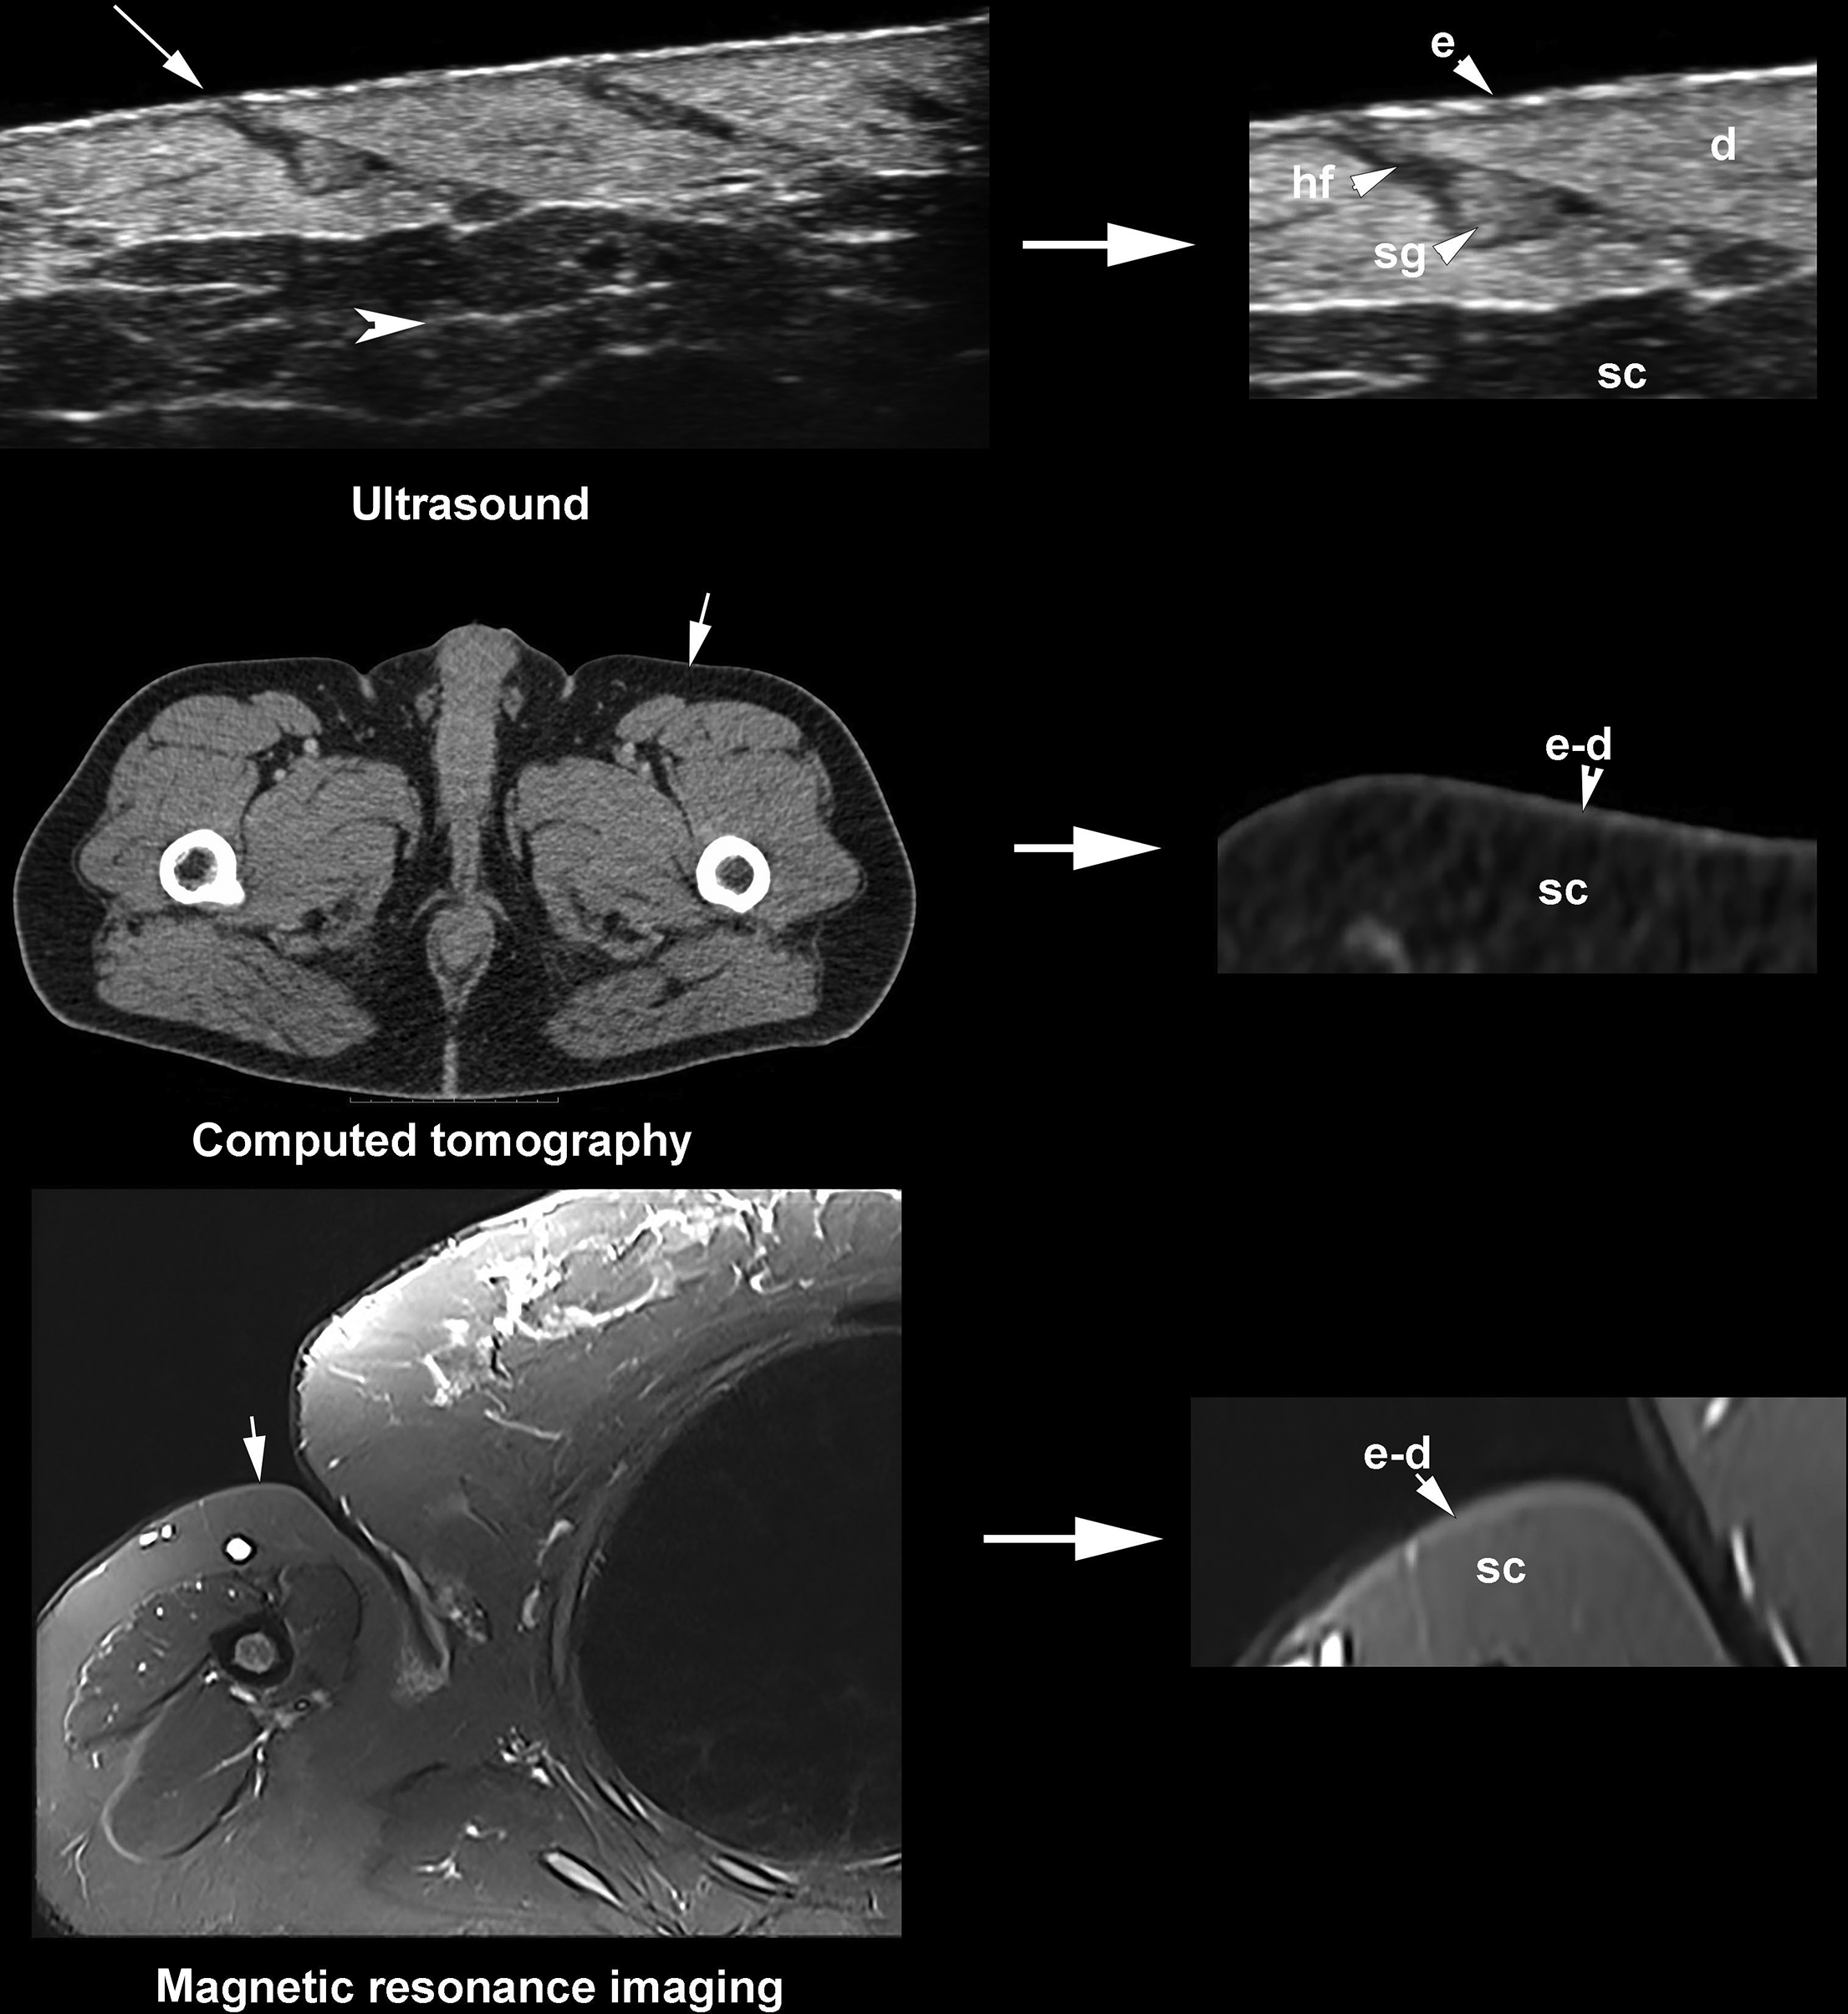

Ultrasound can detect submillimeter subclinical alterations in HS and characterize the blood flow, including type (arterial or venous) and velocity of the vessels noninvasively through color Doppler. The detection of vascularity patterns allows monitoring the degree of inflammation in HS; therefore, it can support activity level discrimination. Furthermore, ultrasound is considered a safe and non-radiating imaging technique that is commonly used in pregnant women ( Fig. 6.1 ).

For detecting early subclinical and submillimetric abnormalities, it is necessary to have ultrasound devices that work with multifrequency probes that present their upper ranges ≥ 50 MHz, which may not be widely available. However, if these ultrasound machines are available, they will allow detection of the following early signs ( Figs. 6.3 to 6.5 ) :

- 1.

Modification of the axis of the hair follicle from straight (slightly oblique) to curved

- 2.

Thickening of the hair follicles and tracts

- 3.

Ballooning of the hair follicles

- 4.

Donor Sign: Dilated hair follicles that donate their keratinous content to fluid collections and tunnels.

- 5.

Sword Sign: Fragments of hair tracts going from the cavity of a dilated hair follicle to the surrounding dermis.

- 6.

Bridge Sign: Communications between adjacent and curved hair follicles. These connections may be conformed by single or multiple bridges between neighboring hair follicles.

- 7.

Two types of fragmentations of the keratin are multifragment and cylindrical. Multifragment is the presence of multiple small fragments of hyperechoic linear fragments within the dilated hair follicles, fluid collections, or tunnels. The cylindrical type is composed of hypoechoic thick bands within the same structures that sometimes may show hyperechoic borders.

The signs significantly associated with the disease’s severity are the presence of “bridge” and “sword” signs and the cylindrical type of keratin fragmentation. Thus, tunnels and fibrotic changes are more frequent in these cases. The rest of the ultrasonographic signs may explain the initial formation of the primary clinical lesions.